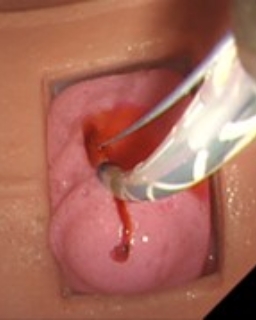

ERCP/ESTは不適切な切開による出血合併症の発生が問題となりますが、出血を再現できるドライシミュレータがありませんでした。

- 出血時はシリンジ操作により拍動性出血を再現可能

- 11~12時方向以外での切開または過剰な切開で出血合併症

出血合併症再現